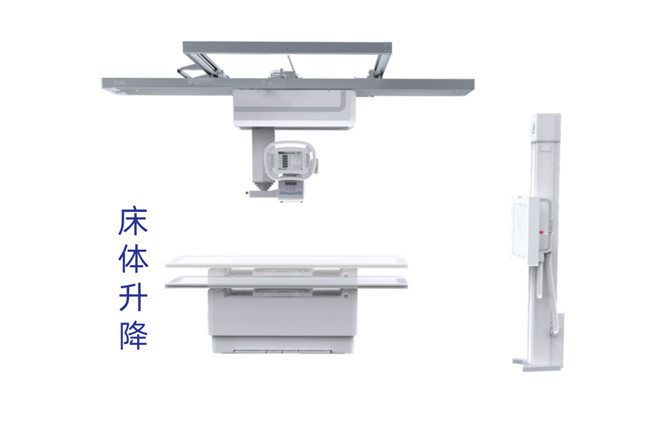

而懸吊式的機械結構以及可伸縮的球管系統可幫助實現無死角擺位,滿足多種體位拍攝的需求,配合智能升降床設計,即使對于輪椅位、移動床病人攝片,普利德多功能懸吊動態DR也能夠自如應對。